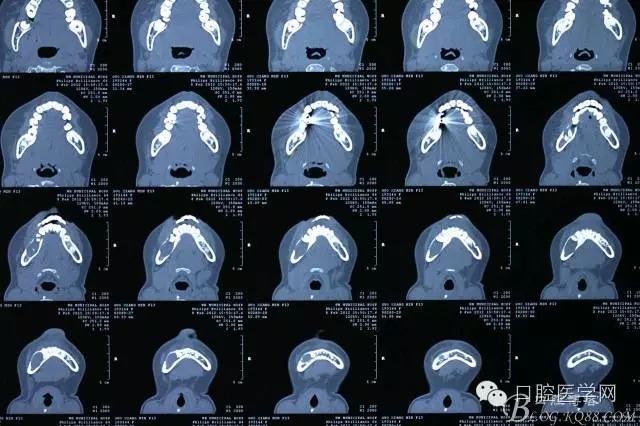

查:右側(cè)第二前磨牙第一乳磨牙恒尖牙頰側(cè)前庭溝隆起,捫有乒乓球感。曲斷及CT示:右側(cè)第二前磨牙第一乳磨牙恒尖牙根尖區(qū)有一囊腫,頰舌側(cè)骨板極薄,牙根無(wú)吸收,第二前磨牙牙根位于囊腫中,第一雙尖牙牙冠遠(yuǎn)中水平向阻生,牙冠位于囊腫中。經(jīng)協(xié)議:手術(shù)摘除創(chuàng)傷大,同意開(kāi)創(chuàng)引流保守治療。